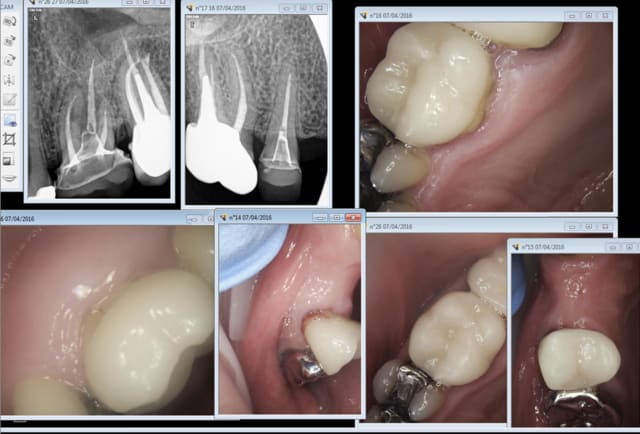

Des fois je tombe sur quelques unes de mes réalisations. Ici une molaire et une prémolaire de 2009. Ca n'a pas l'air de bouger.

J'ai posté ce cas pour sa tenue dans le temps pas pour son esthétique ! -)))